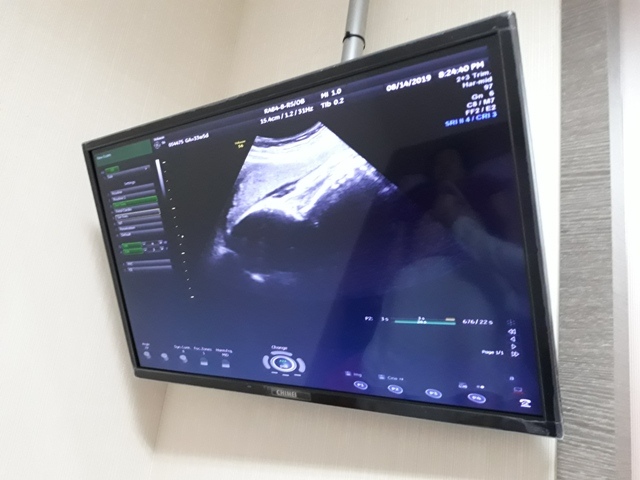

當小純進入診間看診時,我並沒有進去,因為小純說,有時男生不能進去,會被請出來。在外頭等待的我感到很緊張,不久之後,謢理人員請我進入診間,我嚇了一跳,想說發生什麼事了,進入之後,得知小純真的懷孕了,而且已懷了九星期又五天。看診的醫師說,驗孕棒第二條線淡淡的,沒想到胚胎照出來那麼大了,說Baby很健康。還說一閃一閃的是他的心跳,有頭、有手、有腳還有臍帶。小純後來說看了內心覺得很感動,才叫我一起進去看。

小純肚子裡的Baby超音波圖↓